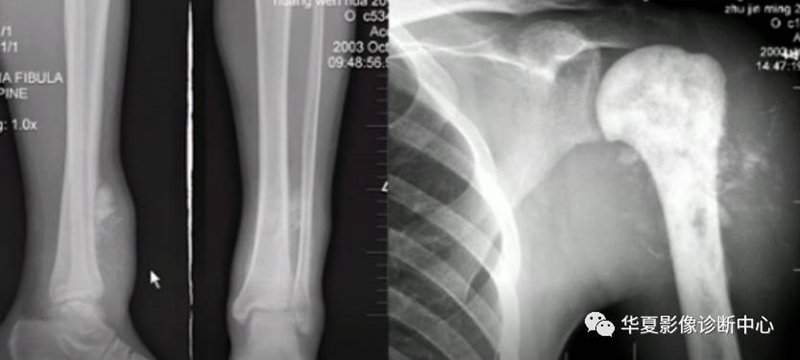

主要有纤维源性、软骨源性及成骨源性肿瘤。

纤维源性肿瘤

软骨源性肿瘤

成骨源性肿瘤